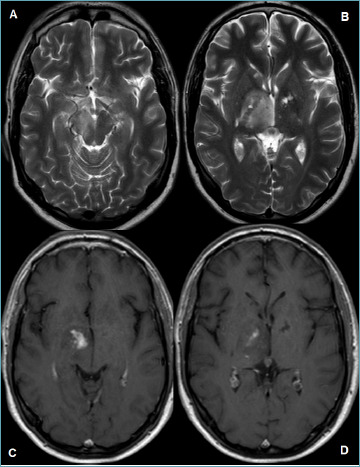

Primary angiitis of the central nervous system (CNS) is an uncommon inflammatory disorder, with highly variable clinical presentation. It needs to be differentiated from several mimickers, such as CNS involvement in systemic vasculitides, connective tissue disorders, infectious disease, and leukodystrophy as well as neoplastic diseases. The diagnosis requires a combination of clinical and laboratory investigations, multimodal imaging, and histopathological examination, which should be available for confirmation. In the present paper, the histopathological features of primary angiitis of the CNS are described and highlighted to help pathologists avoid misdiagnosis of a treatable acquired disease.

Abstract Image